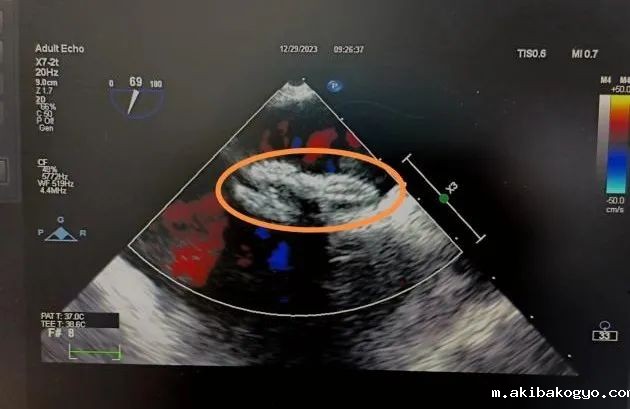

手术于纯超声引导下开展,心外科团队在超声科郇致福高级医生及麻醉科王小雷顾问医生精密配合操作下,顺利将一枚可降解封堵器植入李女士心脏卵圆孔未闭处,展开双盘面、锁定、释放封堵器,顺利完成封堵。

术后超声复查显示,封堵器成型稳定,双盘牢牢贴附房间隔,形态位置良好,无残余分流,封堵效果非常理想,手术顺利成功。